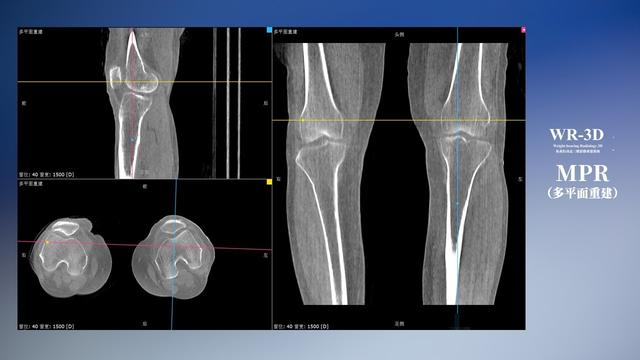

普通平片扫描与WR-3D扫描前后诊断结果对比

与此同时,数字化X线摄影技术相较于CTMRI来说,能快速获取真实、直观、满足临床需要的影像。DR的图像具有图像层次丰富、空间分辨力高、影像边缘锐利清晰、密度分辨力高级细微结构表现出色等特点,针对膝关节解剖结构数字化X线摄影技术应用价值很高,尤其是是对骨小梁与骨皮质的显示非常清楚。在负重位状态下,数字化X线三维摄影扫描与重建,能够更好的呈现受检者关节受力改变的状态。388vip太阳集团科技创新的WR-3D动态三维数字化X线摄影技术,通过数字化X线摄影完成三维扫描并重建三维影像信息,包括MPR多平面重建、MIP重建以及VR绘制。扫描时间短,剂量相较于CT设备大幅缩减,同时成本更低,在临床诊断以及医疗方案制定中具有极大的价值意义。相较于普通平片下的负重位扫描,负重位动态三维扫描摄影技术能够避免二维状态下的组织结构重叠、密度分辨率不足、组织解剖结构难以分辨等问题,WR-3D支持多角度的动态三维摄影观察,能全面的呈现被检查部位在多个角度下三维影像信息,极大的减少了二维负重位检查的漏诊率。